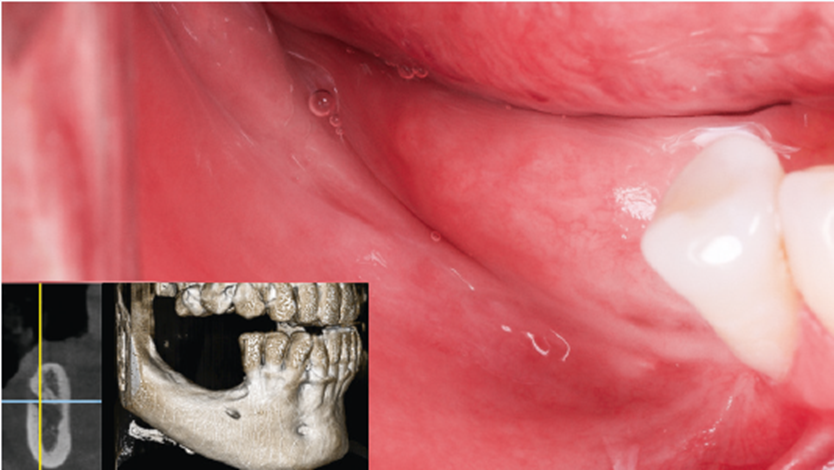

Paciente masculino, 52 anos, compareceu à clínicacom queixa de ausência dentária inferior posterior bilaterale desejo de reabilitação com implantes dentários. Ao exameclínico, verificou-se uma mucosa alveolar fina e a ausênciade gengiva queratinizada nas regiões edêntulas. A tomografiacomputadorizada de feixe cônico (TCFC) evidenciou a reabsorçãoóssea severa, comprometendo a instalação direta dos implantesdentários (Figura 1).